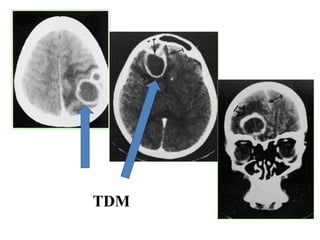

• Hématome extradural : H.E.D

– C’est une urgence neurochirurgicale absolue

– HED se développe en quelques heures et peut

entrainer la mort du patient par engagement 

indication opératoire en urgence

• hématome : collection de sang extra axiale péri

cérébrale entre la table interne et la dure mère de la

voute par plaie de l’artère méningée moyenne

RX DU CRANE:

• TDM en urgence : visualisant

– trait de fracture: en regard de l’hématome

– hématome : formation spontanément

hyperdense en lentille biconvexe

– Effet de masse: refoulement des structures

médianes(faux du cerveau,V3, épiphyse) et

du ventricule homolatéral engendrant un

engagement (signe de mauvais pronostic)

HED